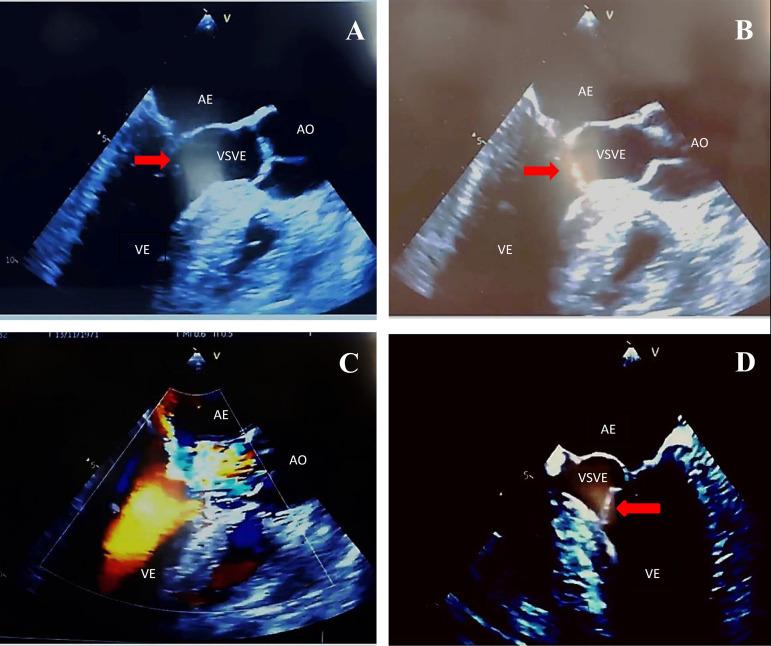

Tumoration in Anterior Leaflet of the Mitral Valve.